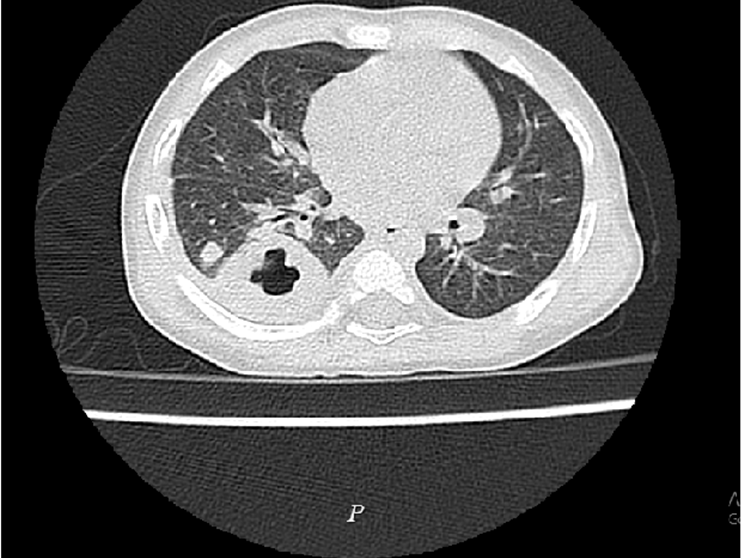

Các bác sĩ Khoa Nhi, Bệnh viện Đa khoa Hùng Vương, ngày 19/8 cho biết kết quả xét nghiệm máu, chụp X-quang tim phổi, cấy máu, chụp cắt lớp vi tính phổ...